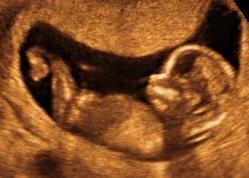

Mødregruppe: Marts 2012

Status på vores graviditeter